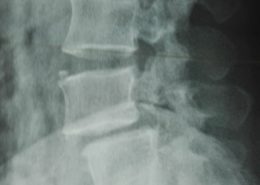

Latest Spine Fixation Technique